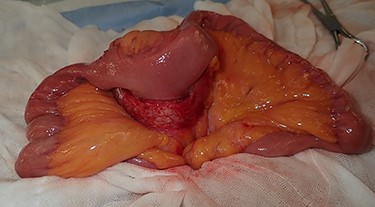

Regarding the intraoperative findings, we explored the abdominal cavity after minimally opening the upper abdomen. The abdominal wall extensively adhered to the small intestine and omentum in the lower abdomen. The adhesions made it difficult to locate the tumor on palpation. Therefore, we decided to identify the tumor using laparoscopy. A laparoscope was inserted from the place of the minilaparotomy wound with protector for pneumoperitoneum, and a 5-mm trocar was placed in the right abdomen. A hard mass could be visually recognized on the mesentery in the lower left abdomen using the laparoscope, and the mesentery was grasped with forceps. Adhesive detachment and abdominal wound extension were performed as much as necessary to remove the tumor from the abdominal cavity. The tumor was extracted under direct vision by partial resection of the small intestine (Fig. 4). The pathological findings revealed dense proliferation of spindle-shaped fibroblasts (Fig. 5a). Immunohistochemically, the tumor cells were positive for β-catenin and negative for S-100 and c-kit (Fig. 5b–d). Based on these findings, a diagnosis of desmoid-type fibromatosis was made. At the 12-month follow-up, the patient had no recurrence or metastases.

The tumor that developed from the mesentery was resected under a minilaparotomy.